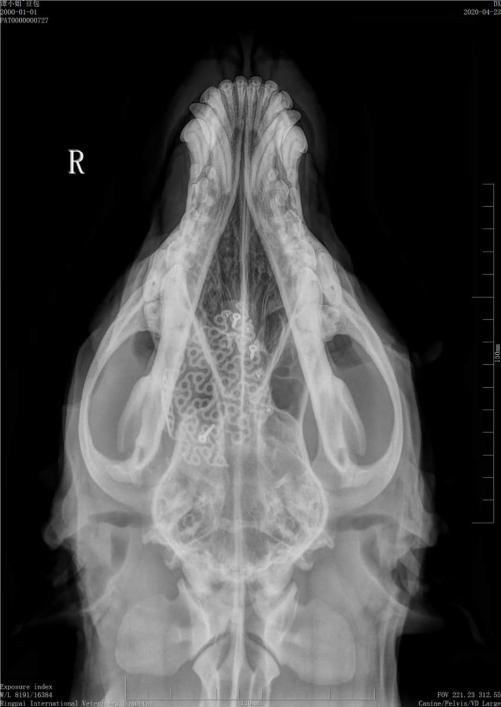

术前影像

李拓医师是神经外科与中兽医专科的“双料专家”。近期一只遭遇车祸的拉布拉多被主人送至瑞派宠物医院太安影像中心院就医,狗狗就诊时头皮已经随呼吸凹陷,经过CT检查颅骨碎裂大面积颅骨缺损情况万分危急。

狗狗颅骨缺损部位的皮下软组织与脑组织直接接触,不仅影响外观,而且脑组织受损危险性增大,一些伴发症状也与此有关,李拓医师团队精心为患宠制订了个性化治疗方案,采用计算机辅助设计和制造技术,采用钛合金补片为患宠进行颅骨缺损修补术。